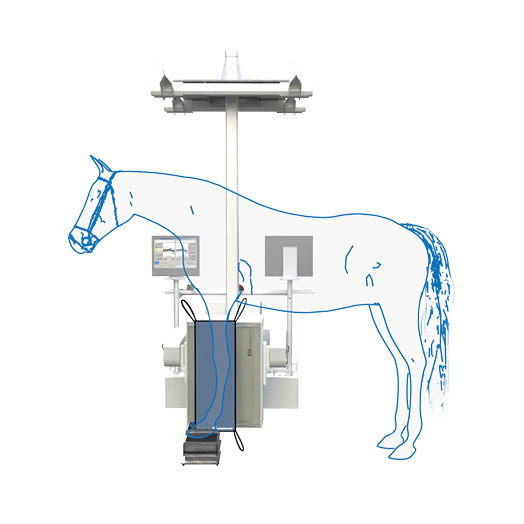

Scintigraphy on a Standing Horse

An ingenious combination of mechanics, electronics, and software makes scintigraphy on a standing horse easily achievable. Experience gained from human medicine, including detector specifications, measurement methods, and processing, as well as feedback from our many customers, has enabled us to achieve the goal of easy and fast diagnosis.

It is compact, robust, and mechanically superior to pendulum suspension systems. The detector support column is mounted approximately one centimeter above the floor, allowing quick and easy movements along any axis of the gantry support. Thus, the gantry operates at a low noise level.